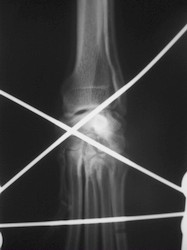

PRÁCTICAS CURSO DE FIJACIÓN EXTERNA PERFECCIONAMIENTO.

Artrodesis carpo.